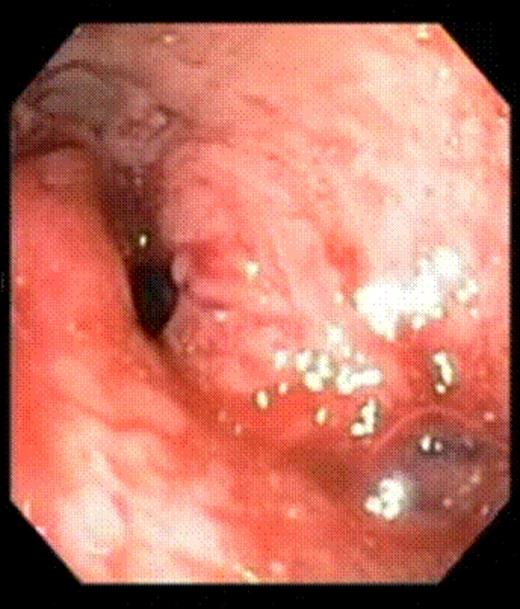

Gastrojejunal stoma immediately after endoluminal gastric pouch plication

This 47-year-old man underwent a RYGB with a 30cc pouch, a 12mm circular stapled GJ and a 150cm long Roux limb in 2005. He lost 75kg with a reduction of BMI of 23.3 (63.7 to 40.4), achieving his lowest weight 3.25 years after his RYGB. The patient started experiencing dumping syndrome and regained 7kg in weight over the next 11 months, going up to a BMI of 42.5. An upper GI series x-ray showed an enlarged gastric pouch. An oesophago-gastro-duodenoscopy (OGD) showed a dilated GJ with loss of restriction. As an alternative to an open or laparoscopic revision, the patient elected to undergo endoluminal surgery using the StomaphyX™ device. The procedure was carried out under general anesthesia. An upper endoscopy was first performed to identify the anatomical landmarks of the pouch. The pouch length was noted to be 7 cm. The GJ was again observed to be widely dilated. The endoscope was then inserted through the shaft of the StomaphyX™ device, and the device and endoscope were introduced in tandem transorally into the pouch under continuous visualization. Once inside the pouch, vacuum was employed to draw large folds of gastric pouch wall tissue into the lumen of the device. With the gastric pouch wall on suction, the pouch wall was circumferentially plicated with serial firings of 6mm 3-0 polypropylene fasteners. This plication was in performed at two levels, one at 1 cm above the GJ anastomosis and one at 1 cm below the gastro-oesophageal junction. In total, 22 fasteners were delivered. A completion endoscopy was performed after the plication which showed that the 7-cm pouch had been reduced to 3 cm in length. The luminal diameter as well as the width of the GJ anastomosis was also significantly narrowed. The procedure took 40 minutes to perform with minimal intra-operative bleeding. There were no perioperative or postoperative complications.